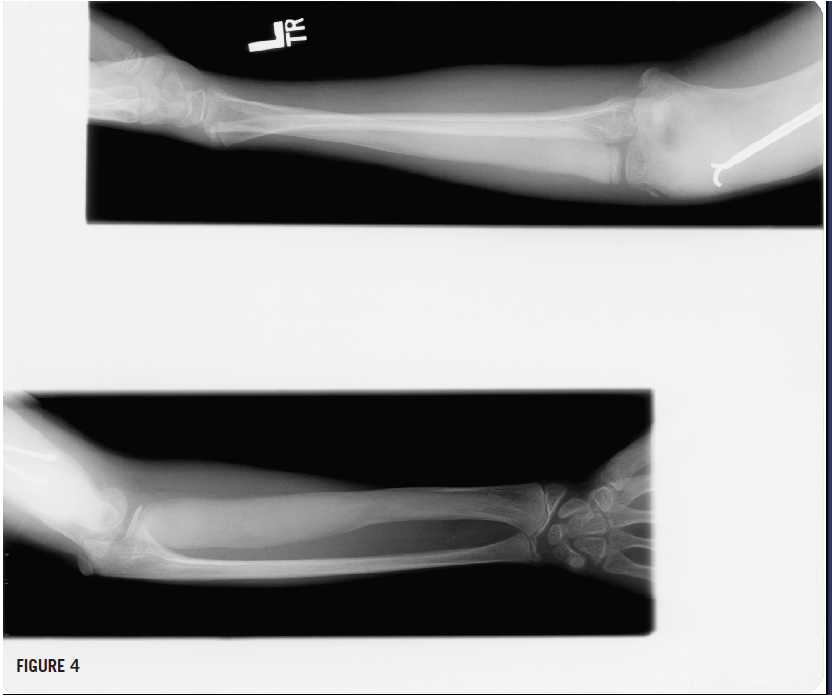

Radiographs of the left humerus showed lesions with ground-glass opacity and a Madelung deformity of the wrist (Figures 3 and 4), suggesting polyostotic fibrous dysplasia (FD). Bone age and chronologic age were similar. Results of magnetic resonance imaging of the brain were normal.